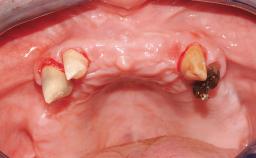

Rehabilitating an Edentulous Maxilla with a Fixed Dental Prosthesis Following Provisional Immediate Loading

This case features the flapless computer-guided placement of 7 bone-level implants, distributed to provide maximal support for the prosthetic framework. A rigid one-piece metallic framework was utilized as an interim restoration to reduce the risk of fracture associated with this prosthetic design. As part of the clinical examination, the SAC Assessment Tool was used, resulting in a surgical and restorative risk classification as “complex”.

Soft Tissue Contour and Volume Slightly compromised